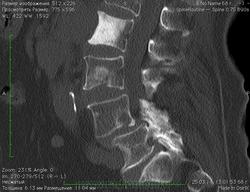

Женщина 65 лет. В анамнезе рак почки T3N2M1.

Пришла от онколога с жалобами на боли в спине, просят исключить метастатическое поражение поясничных позвонков.

Собственно мой вопрос - как бы вы объяснили изменения L2?

Вероятно мтс... А в анамнезе гемангиому L2 не лечила?

Просят исключить? Варианта два:

- написать "нельзя исключить, рек. ПЭТ КТ",

- написать изменения в позвонке нехарактерны для мтс почечно-клеточного рака, больше данных за склерозированный мтс как результат химиотерапии.

А что боли в спине, не мудрено, там листез на листезе, да плюс грыжи, если в медиастинальном окне посмотреть.

Вопрос в другом - может ли какая-то форма рака почки давать остеобластические метастазы. Я всю жизнь считал что подавляющее большинство метастазов рака почки - литические.

Я не корифей. Работал бы в онкодиспансере, среди потока метастазов, был бы им. А так - ОЛС (общая лечебная сеть). НО, часто встречая остеосклеротические очаги в позвонках при контроле пациентов  с установленными раками различных локализаций, для себя (ДЛЯ СЕБЯ) решил, что это склерозированные метастазы.

А сначала даже хотел статью писать об остеобластических метастазах при раках, где типичными считались метастазы остелитические. Но остановился на стадии литобзора.